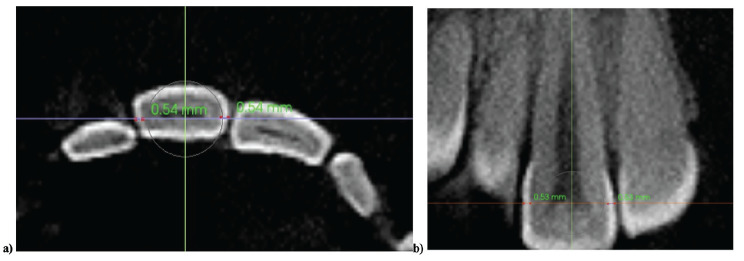

Objective: This study aimed to explore variations in enamel thickness to provide guidelines for optimal interproximal enamel reduction in an untreated population using cone-beam computed tomography (CBCT).

Methods: CBCT scans of 100 orthodontic patients (51 Caucasian, 49 patients of Somalian descent; aged (12-18) were analyzed retrospectively. Enamel thickness was measured at the mesial and distal contact points of teeth from the second molar to the central incisor in both the maxillary and mandibular arches. Linear mixed models were employed to assess the effects of ethnicity, gender, anterior-posterior region, and mesial-distal proximal surfaces on enamel thickness. Fixed effects were estimated using the Kenward-Roger method, and a random intercept with an unstructured covariance matrix was included to account for within-subject variability. Ethnicity-specific residual variances were also modeled. Statistical significance was set at p<0.05.